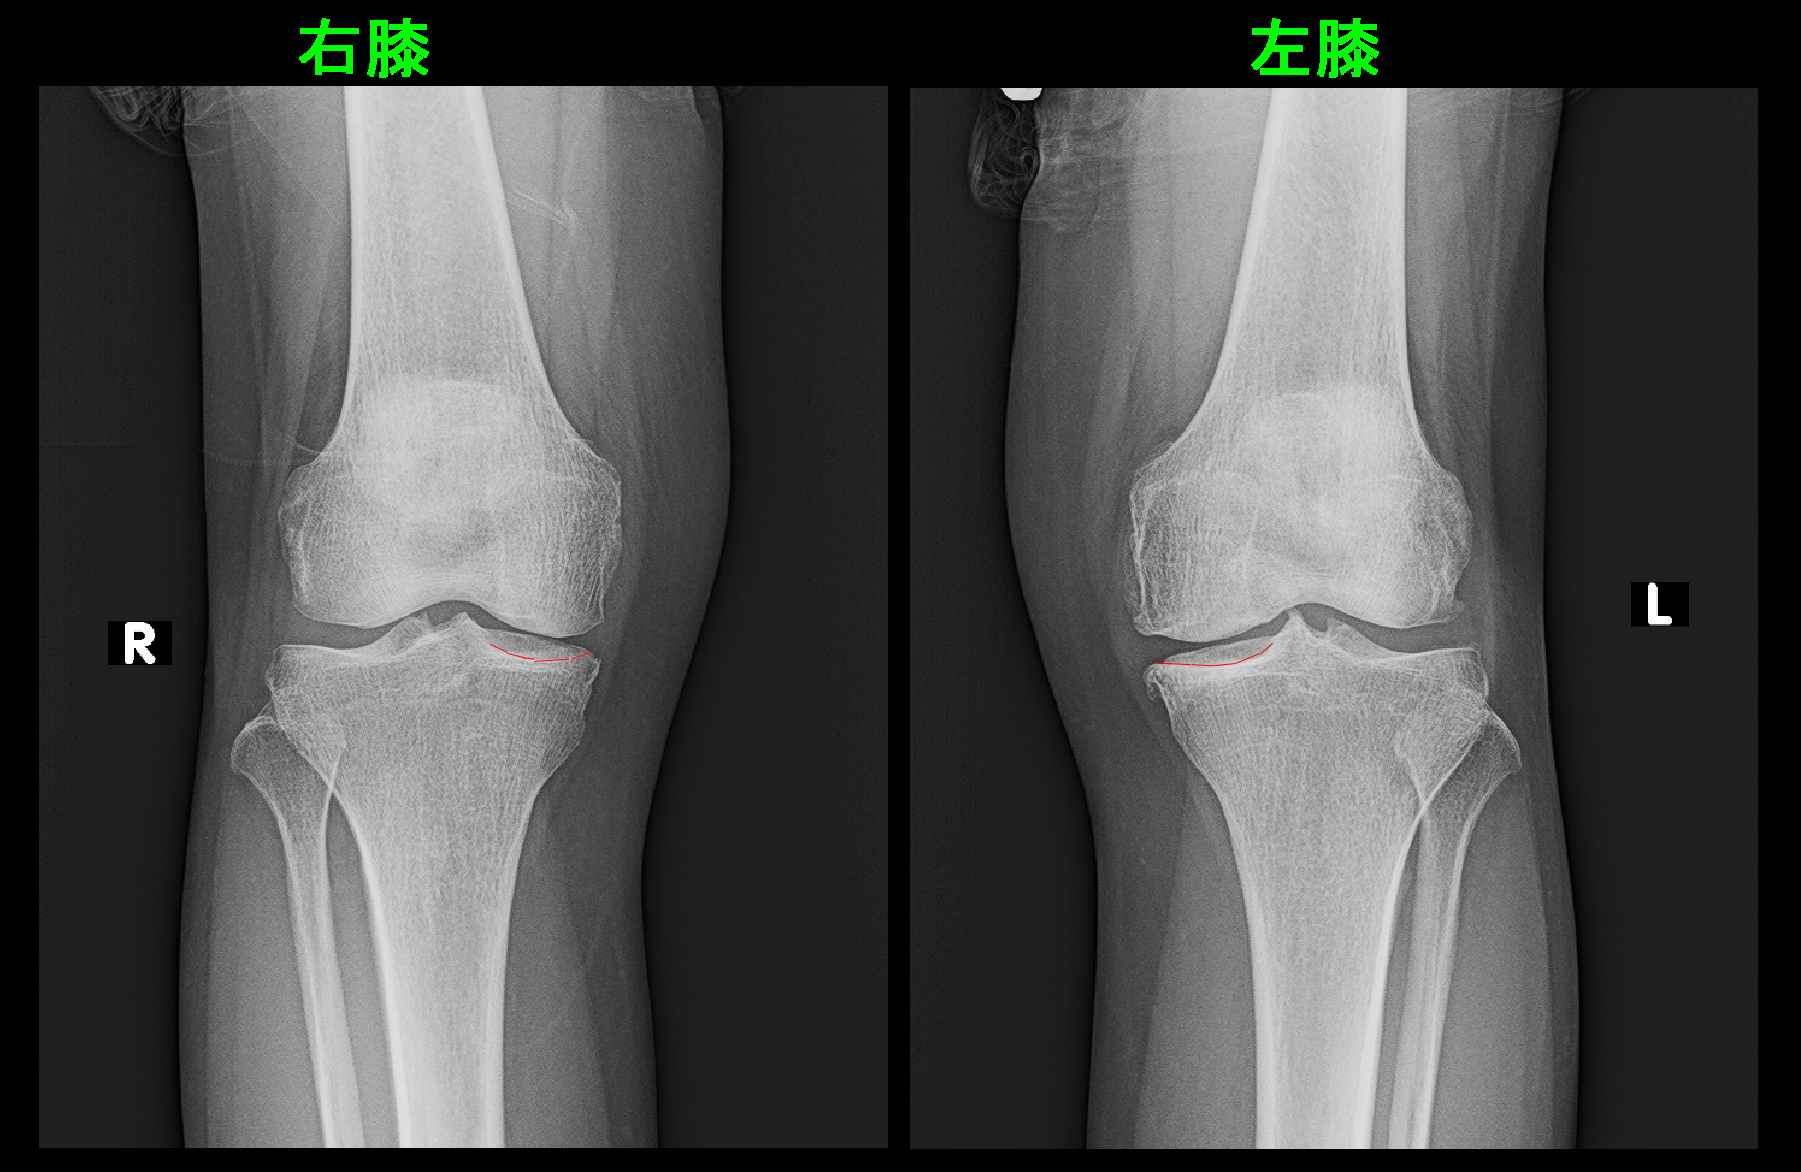

63才女 Xp3.jpg

レントゲン像は77才で仙台のダンス大会に出場した頃のものです。右膝に比して左膝では大腿骨の内外縁での骨棘形成が目立ちますが、関節の隙間の狭小化は左右とも目立たず、レントゲン所見では軽度の変形性膝関節症の状態です。